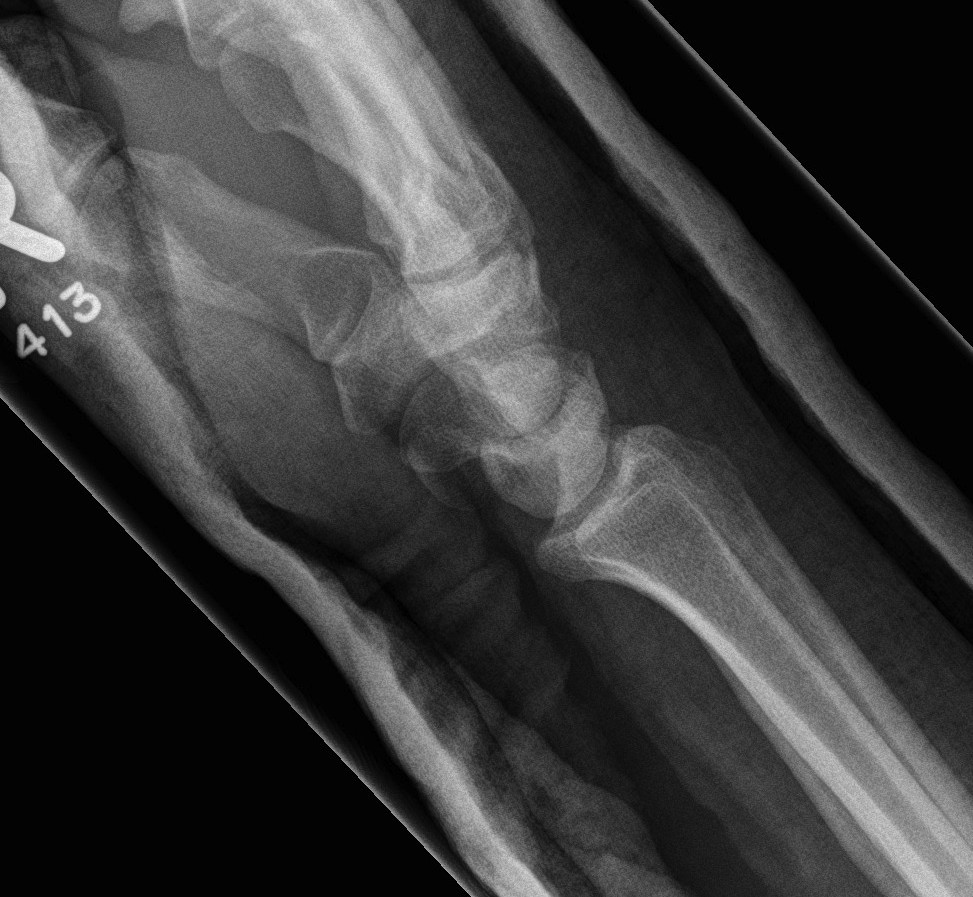

X-ray

Disruption of Gilula's 3 smooth carpal arcs

Progressive Injury

1. Capitate dorsal

- lunate remains with radius

- lunate looks triangular on AP

2. Lunate dislocates

- usually volar